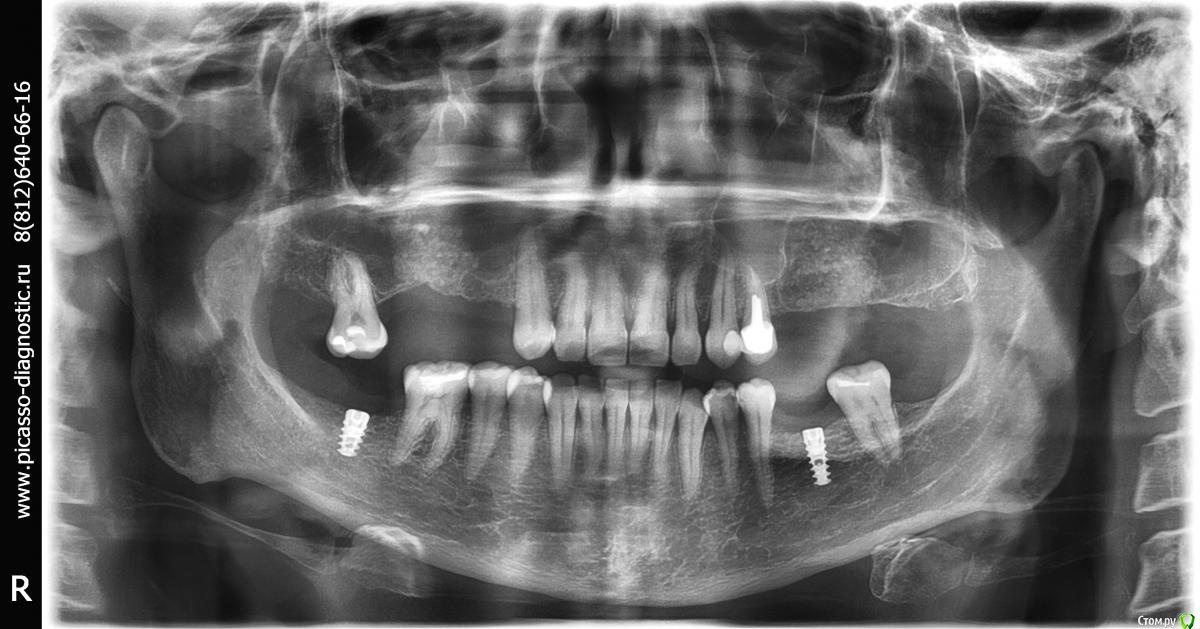

Evikrol Опубликовано 29 марта, 2015 Автор Поделиться Опубликовано 29 марта, 2015 (изменено) открытый синус лифтинг или 8 мм? Изменено 29 марта, 2015 пользователем Evikrol Ссылка на комментарий

Tabula Rasa Опубликовано 29 марта, 2015 Поделиться Опубликовано 29 марта, 2015 (изменено) можно отстучать и поставить 8,правда по ширине не очень Изменено 29 марта, 2015 пользователем IlyaPM Ссылка на комментарий

bullbull Опубликовано 30 марта, 2015 Поделиться Опубликовано 30 марта, 2015 8888.jpgоткрытый синус лифтинг или 8 ммЗакрытый и 10 1 Ссылка на комментарий

Евгений Ходыкин Опубликовано 30 марта, 2015 Поделиться Опубликовано 30 марта, 2015 8888.jpgоткрытый синус лифтинг или 8 мм? Вы в замер высоты кортикальную пластинку то вообще не включили. Ссылка на комментарий

Evikrol Опубликовано 30 марта, 2015 Автор Поделиться Опубликовано 30 марта, 2015 А есть смысл 10 толкать, может лучше 8 заглубить? Ссылка на комментарий